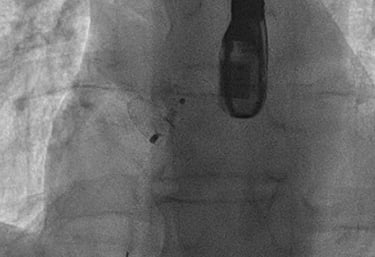

CORONAROGRAFIA

La Coronarografia è l’esame piu’ approfondito per valutare la presenza di restringimenti (“stenosi”) a carico delle arterie coronarie, ovvero delle arterie che nutrono il cuore. Viene effettuata tramite utilizzo di appositi cateteri che vengono inseriti attraverso l'arteria radiale o femorale. Per acquisire le immagini viene utilizzato un liquido chiamato “mezzo di contrasto” che opacizza il lume delle arterie mescolandosi al sangue. Le immagini vengono acquisite da un macchinario che emette una debole radiazione e registra le immagini.